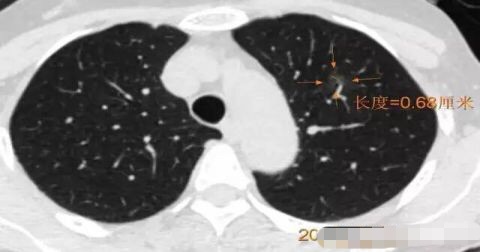

病例1 .

2014年 首次发现右肺上叶GGO,病灶直径8.3毫米, 2016年复查发现右肺上叶GGO,病灶直径12.4毫米。2年大约生长4毫米,平均1年生长2毫米。2016年手术病理结果:浸润性腺癌。

2016年病灶直径12.4毫米